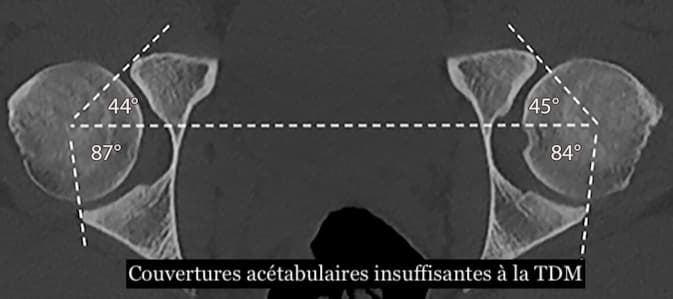

Dysplasie de hanche : la modélisation statistique de la forme pour prédire son évolution

Une technique décrite dans un article de la Revue Radiology et utilisant des images échographiques pour déterminer la profondeur et la forme du cotyle de la hanche peut prédire avec précision l’évolution d’une dysplasie de hanche chez les nourrissons. Les chercheurs ont utilisé la modélisation statistique des formes pour améliorer le diagnostic prédictif, ce qui pourrait significativement réduire les surtraitements pour cette pathologie.

Quelle évolution à moyen terme pour les dysplasies de hanche stables de Graf 2 ?

Il n'y a pas de consensus sur comment et quand traiter la dysplasie stable de la hanche (type Graf 2, tel que déterminé par le système de classification Graf). On estime qu'environ 80 % des hanches Graf 2 stables évolueront comme normales sans traitement. Mais comme il n'y a actuellement aucun moyen de différencier les deux évolutions de cette pathologie, un grand pourcentage de cas stables sont susceptibles d'être surtraités, selon l'auteur principal d’une étude publiée sur le sujet dans la Revue Radiology, le Pr Ralph JB Sakkers, du département de chirurgie orthopédique du centre médical universitaire d'Utrecht (Pays-Bas).

Le système de classification Graf est couramment utilisé pour évaluer la dysplasie de la hanche, mais il a des limites. Les patients sont classés par groupes, en fonction de l'angle acétabulaire sur les images échographiques. Cet angle est dérivé de la profondeur et de la forme du cotyle de la hanche où s'adapte la tête du fémur. Le système Graf présente une grande variabilité et une faible concordance dans toutes les mesures de dysplasie de la hanche rapportées, la qualité de l'image échographique et l'apparence anatomique de l’articulation pouvant être affectées par le positionnement de la sonde.

Le système de classification Graf est couramment utilisé pour évaluer la dysplasie de la hanche, mais il a des limites. Les patients sont classés par groupes, en fonction de l'angle acétabulaire sur les images échographiques. Cet angle est dérivé de la profondeur et de la forme du cotyle de la hanche où s'adapte la tête du fémur. Le système Graf présente une grande variabilité et une faible concordance dans toutes les mesures de dysplasie de la hanche rapportées, la qualité de l'image échographique et l'apparence anatomique de l’articulation pouvant être affectées par le positionnement de la sonde.

La modélisation statistique de la forme par ultrasons est une méthode alternative qui quantifie la forme de l'image de la hanche avec plusieurs points de référence qui ont chacun une coordonnée X et une coordonnée Y dans l'image échographique 2D. Elle offre des avantages potentiels par rapport aux modèles prédictifs existants. « En quantifiant l'image de la hanche avec une modélisation statistique de la forme, beaucoup plus de données sont extraites des images échographiques par rapport aux méthodes actuelles utilisées », poursuit le Dr Sakkers.

Dans cette étude, le Dr Sakkers et ses collègues ont analysé le pouvoir prédictif de la technique chez 97 nourrissons atteints de dysplasie stable de la hanche. Ils ont développé une modélisation statistique de la forme sur des images échographiques de base, puis ont corrélé le modèle avec une dysplasie persistante de la hanche à l'échographie après 12 semaines de suivi et une dysplasie résiduelle de la hanche sur les radiographies pelviennes vers l'âge d'un an. Les résultats ont montré que la modélisation statistique de la forme prédisait avec précision quelles hanches étaient devenues normales ou restaient dysplasiques. Ce processus a également identifié les hanches qui ont bénéficié d'un traitement avec le harnais Pavlik, une attelle souple qui favorise le développement normal de l'articulation de la hanche.